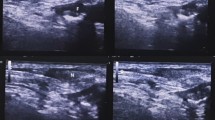

No complications due to ICG injection were observed, either at the injection site or systemically. The median time taken to observe the TD from the injection time was 60 min (range 30–330). Seventy-six cases were performed using Stryker’s 1688 AIM HD system, three under Karl Storz Rubina, and 20 under Karl Storz OPAL 1 S. The TD was clearly delineated brightly along its entire length in 93 patients (94%) and was not seen in six patients. Real-time lymphography was performed in 73 cases using the overlay mode (available only in Stryker’s 1688 AIM HD and Karl Storz Rubina systems), where real-time NIR-ICG guidance was obtained by superimposing fluorescent on white light images. Minor variations in TD were noted in 28 patients (28%). The most common variation observed was saccular dilatation in 14 patients. Other variations noticed were duplication of a part of the duct in four, fusiform dilatation in three, plexiform variation in five, and loop formation and accessory duct joining the main duct in one (more than one anomaly seen in few patients).

Normal fluorescent TD appeared bright green and located between the azygous vein and aorta (Fig. 1). Figure 2 shows normal TD in white light, with the Karl Storz OPAL 1S HD system and Rubina system. NIR-ICG guidance facilitated real-time recognition and clipping of the TD and its tributaries, ensuring a safe surgery (Fig. 3). In 16 cases, the TD was ligated to ensure resection-free margins, while in the three cases, the main TD was preserved, and only tributaries were clipped and ligated to achieve complete lymph node dissection. The significant usefulness of real-time NIR-ICG guidance was observed in patients undergoing salvage esophagectomy or post-thoracic radiation, where extensive thoracic fibrosis blurs the dissection planes (Fig. 4). All patients were followed up for 30 days after surgery, and no patient had chyle leak or adverse reactions related to ICG.

Normal fluorescent thoracic duct lymphography in a patient undergoing minimal access esophagectomy in a semi-prone position. Panel A displays the white light thoracoscopic image, where the TD is not visible. Panels B to D reveal the normal fluorescent thoracic duct lymphogram: B in overlay mode, C in fluorescent mode, and D in SPY Env mode

A Thoracoscopic white light image of the thoracic duct. Note that the TD is visible as a faint tubular structure. B NIR-ICG image of the thoracic duct corresponding to the image in Panel A (Karl Storz OPAL 1S HD system). C Real-time dissection of the thoracic duct in an integrated 4 K and 3D system (Karl Storz Rubina) in overlay mode. D Supra-azygous part of the thoracic duct in the Stryker 1688 HD AIM system